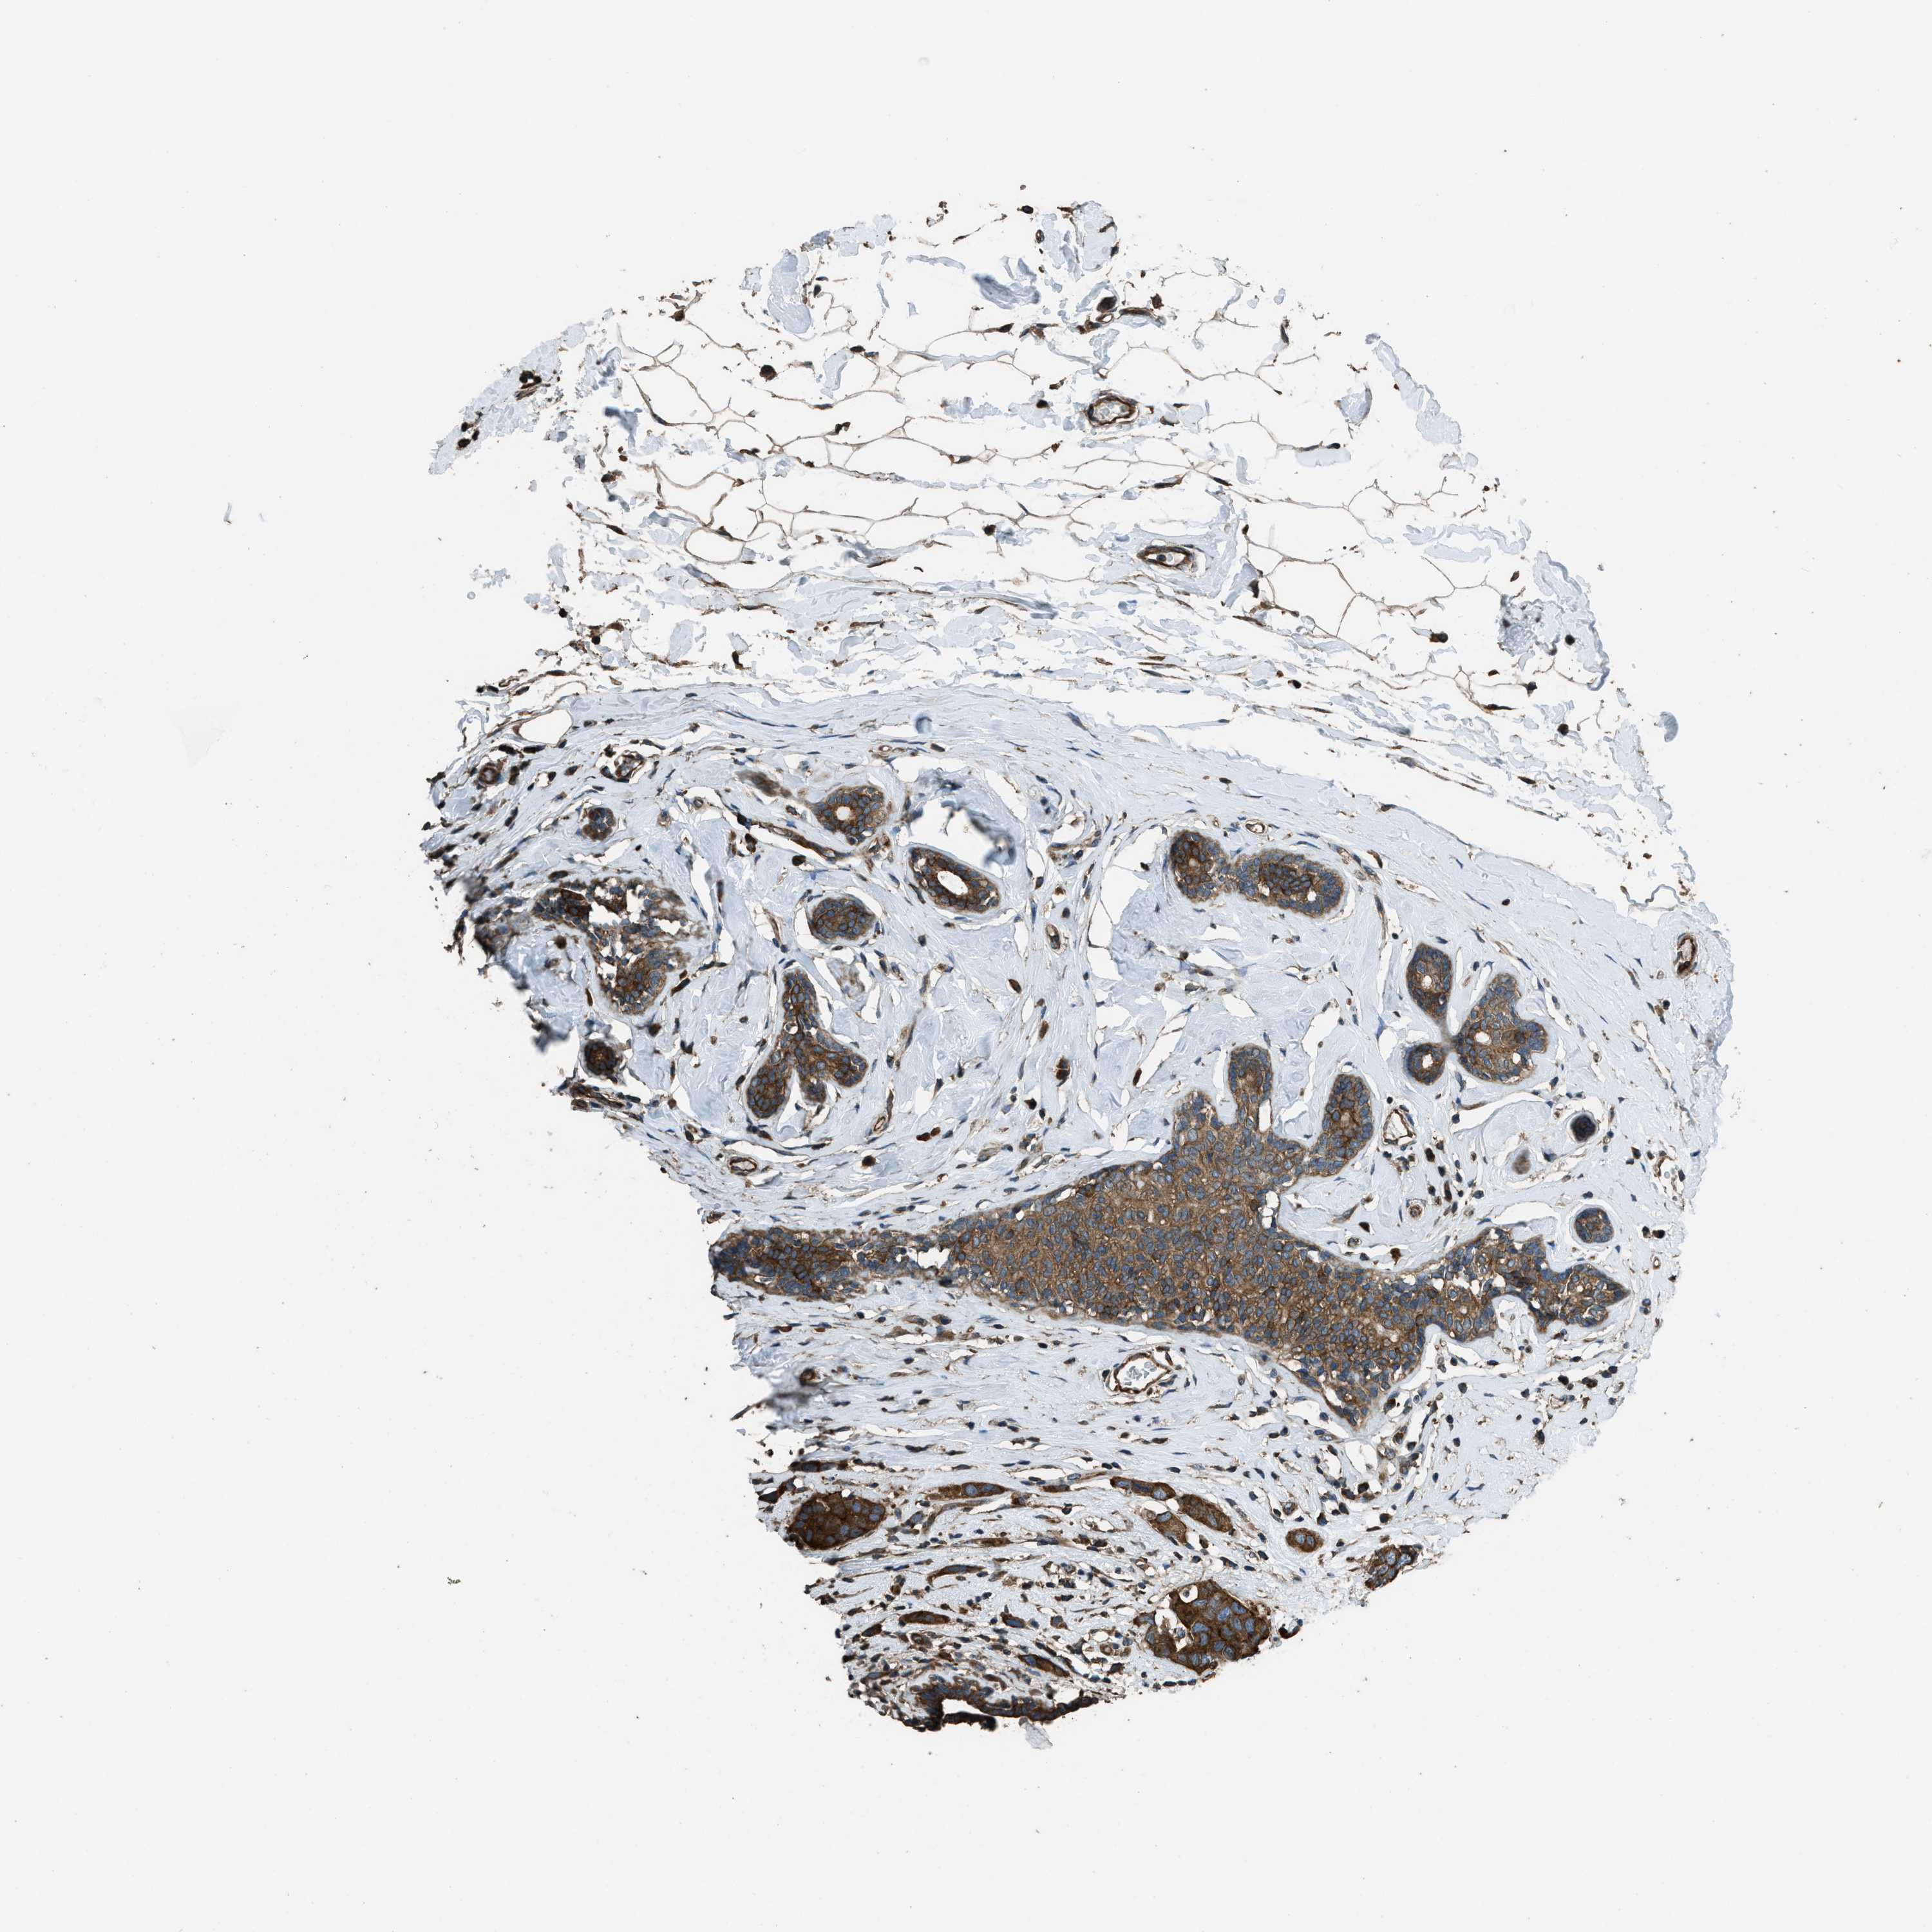

BRCA TCGA BRCA VALIDATION PROTEIN EXPRESSION

ANTIBODIES

AND

VALIDATION